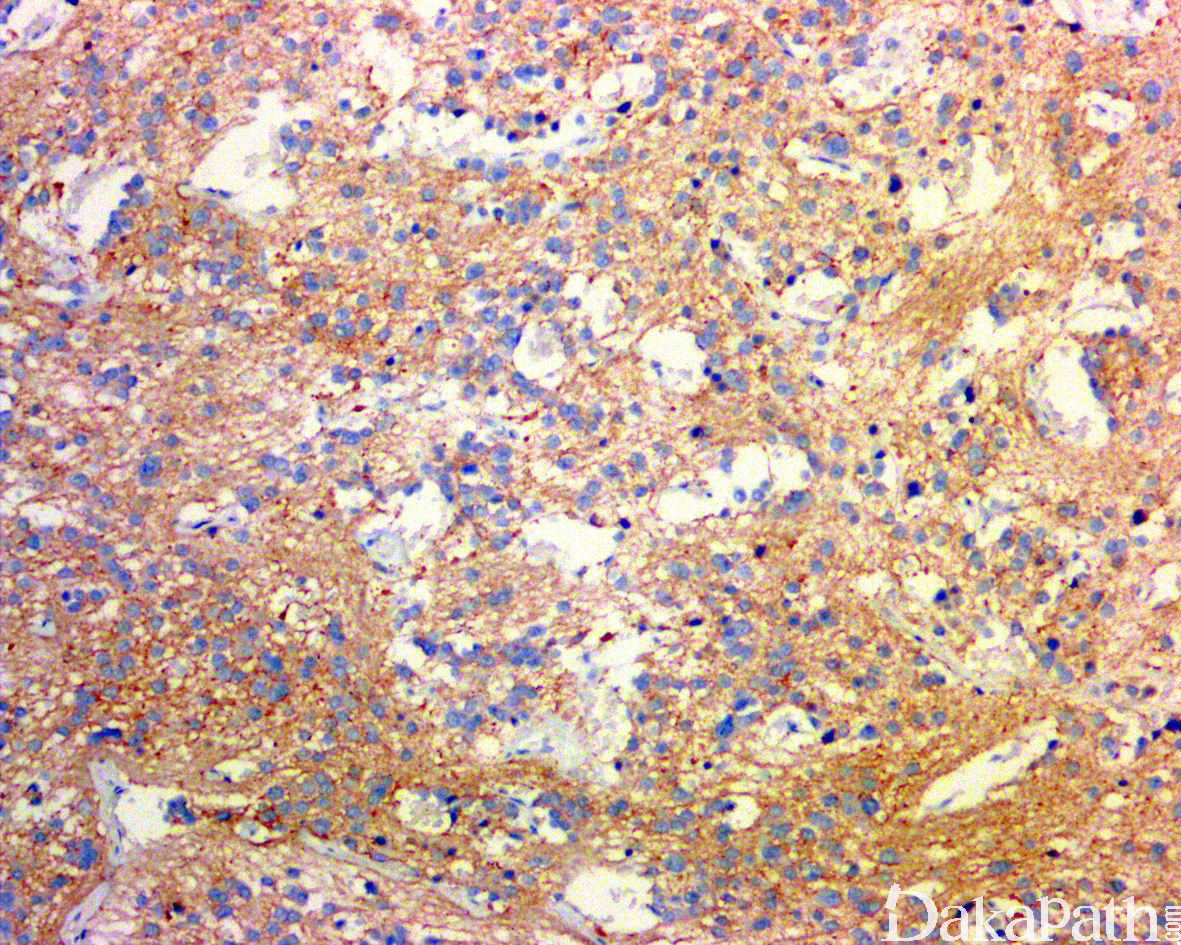

免疫组织化学染色:

NSE 弥漫强阳性、NF、Leu-7. PHXO2B 等阳性;亦常见 synaptophysin、chromogranin、CD56 及 PGP9.5 阳性。未分化的神经母细胞弥漫表达 cyclind1 而神经节细胞不表达,GFAP、MBP、CD99 和 β-2 微球蛋白均为阴性。施万间质呈 S100 阳性。与 N-MYC 扩增相关的肿瘤可过表达 N-myc。